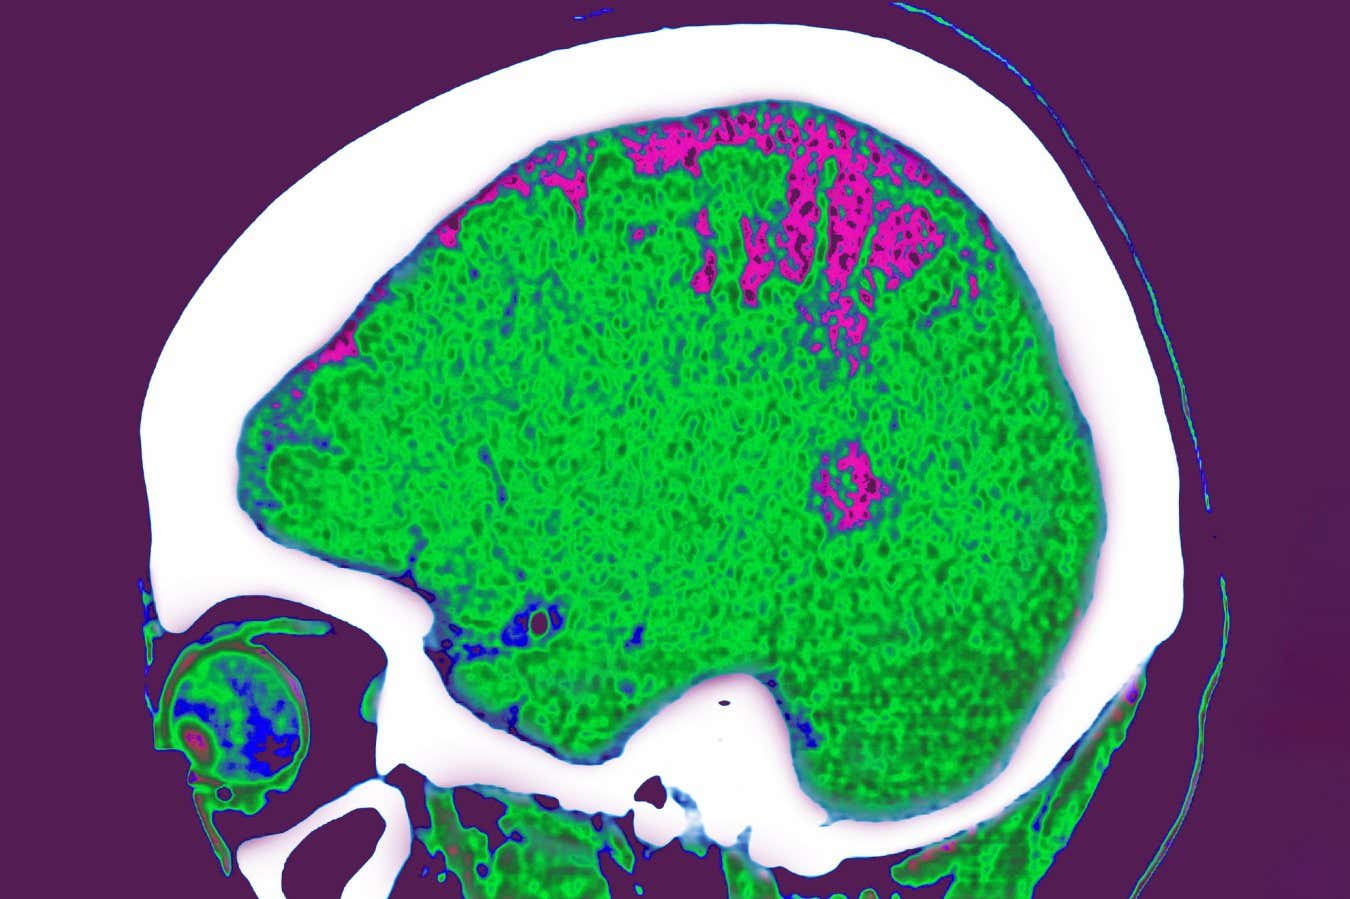

CAVALLINI JAMES/BSIP/Getty Images

The effects that our fat has on our movement, emotions and even our risk of Alzheimer’s disease may differ depending on where in our body it is located.